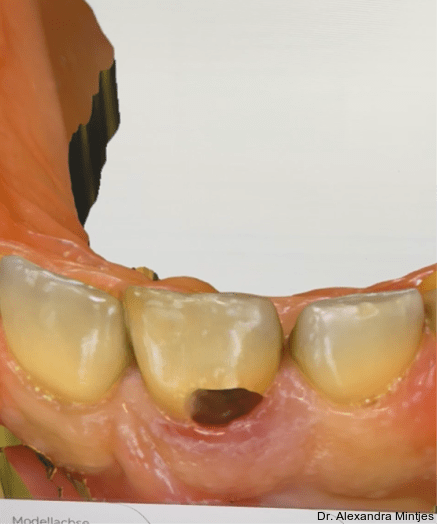

Die Behandlung erfolgte in mehreren präzisen aufeinander abgestimmten Schritten. Zunächst wurde die alte Kompositfüllung vollständig und atraumatisch entfernt, ohne eine Blutung der Schleimhaut zu provozieren. Nur durch das minimalinvasive und vorsichtige Vorgehen bei der Entfernung der insuffizienten Kompositfüllung konnte die Blutungsfreiheit erreicht und somit eine solide Grundlage für die folgenden Behandlungsschritte gewährleistet werden. Anschließend wurde die weiche Zahnhartsubstanz mithilfe eines Rosenbohrers sorgfältig exkaviert (Abb. 3). Überschüssige Guttapercha wurde ebenfalls abgetragen, um eine saubere und stabile Basis zu schaffen.

Parodontaler Befund und temporäre Versiegelung

Die Sondierung ergab eine vertikale Defektausdehnung von etwa sechs Millimetern bei einer Taschensondierungstiefe von lediglich zwei Millimetern. Dies wies somit auf eine parodontale Gesundheit hin. Der gereinigte Defekt wurde anschließend mit einem lichthärtenden Flow-Komposit versiegelt, um Unebenheiten auszugleichen und die Adaptation der geplanten CEREC-­Keramikrestauration zu optimieren (Abb. 4).